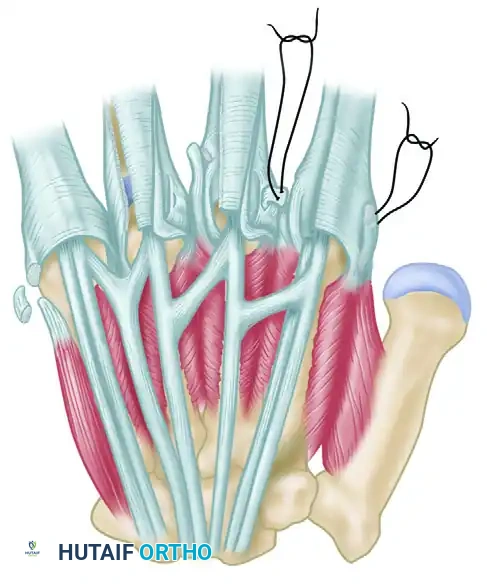

5. Extensor Tendon Tenodesis

In cases where the extensor mechanism is highly unstable, simple imbrication may fail over time.

* Perform a tenodesis of the extensor tendon to the base of the proximal phalanx.

* This can be achieved using small suture anchors placed into the dorsal base of the proximal phalanx, or by passing nonabsorbable sutures through transosseous drill holes. This anchors the centralized tendon, preventing recurrent ulnar subluxation during active flexion.

Additional Rebalancing Procedures

- Abductor Digiti Quinti (ADQ) Release: The ADQ is a powerful ulnar deviator of the little finger. Excise a segment of the ADQ tendon to relieve its ulnar pull on the fifth digit.

- First Dorsal Interosseous (FDI) Advancement: To increase the radial pull on the index finger, the FDI tendon can be shortened or advanced distally.

- Extensor Indicis Proprius (EIP) Transfer: When the index finger exhibits marked, recalcitrant ulnar deviation, the EIP tendon can be detached from its insertion, routed radially, and transferred to the first dorsal interosseous muscle or the radial collateral ligament to reinforce radial deviation and extension.